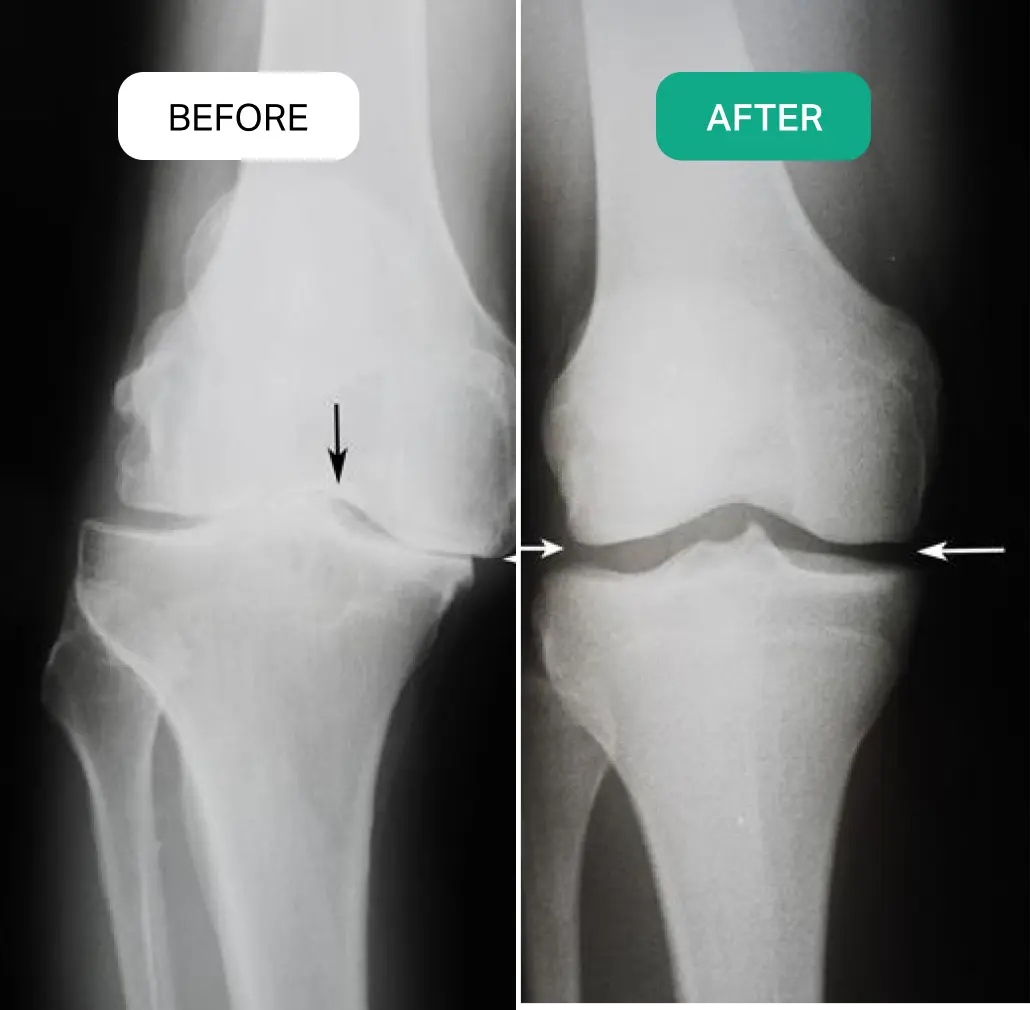

"Your Knees Are Slowly Losing Their Strength Because the Cartilage Is Breaking Down and Your Body Isn’t Producing Enough Collagen to Repair It"

If You Can Still Walk Even for a Few Minutes Without Pain — There’s Still Hope!